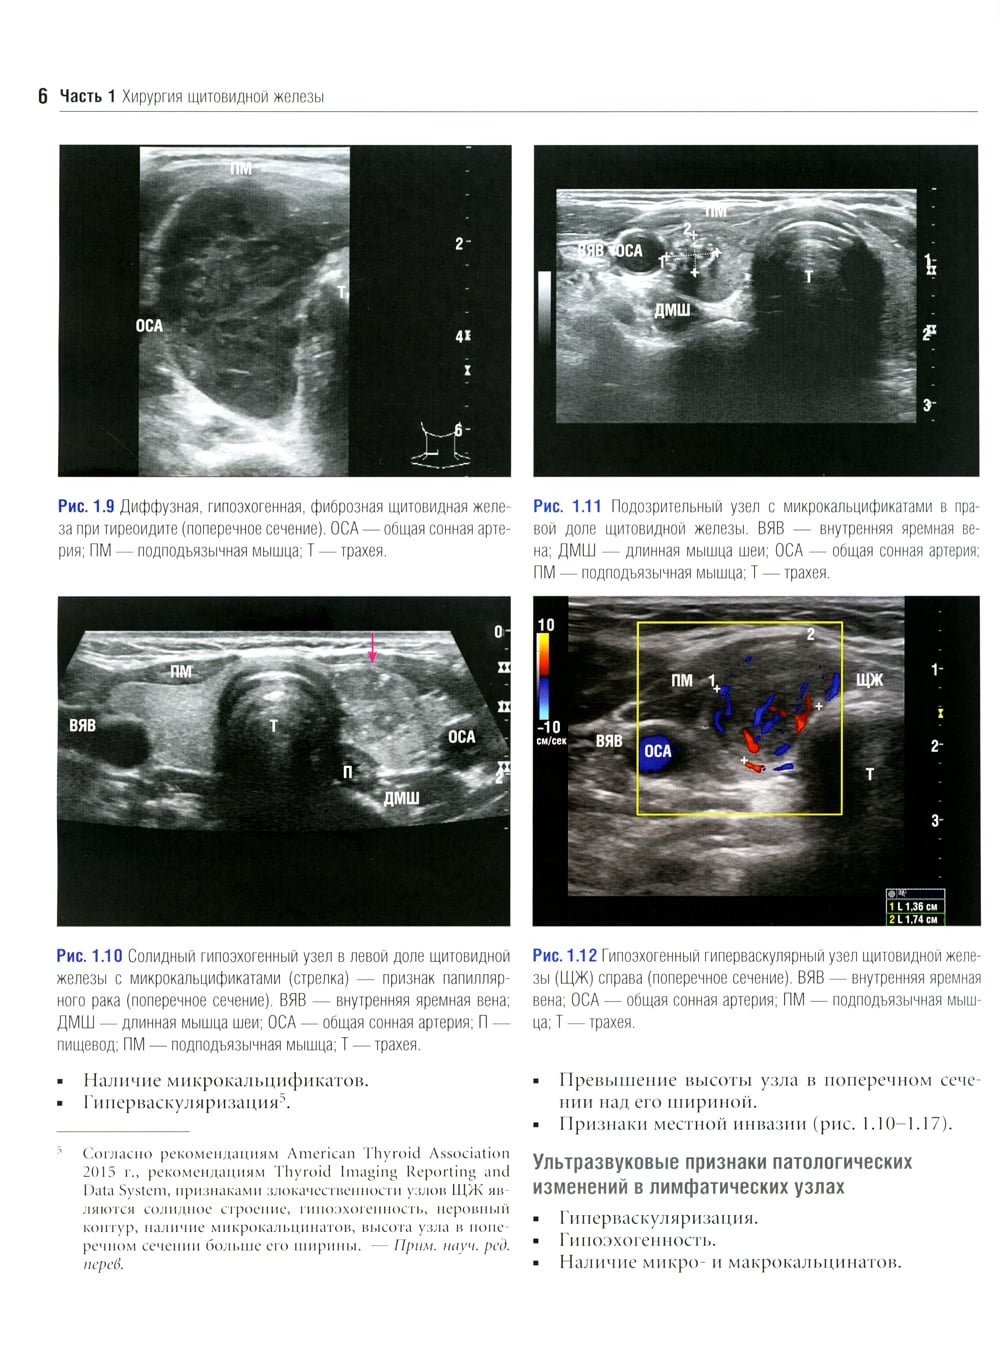

Данное издание представляет собой великолепно иллюстрированный хирургический атлас. В нем рассмотрены методы ультразвукового исследования шеи, молекулярно-генетическое тестирование пациентов с узловыми образованиями в щитовидной железе, робот-ассистированные хирургические методы, техника эндоскопических операций при эндокринных опухолях, хирургия при рецидиве заболевания, аутотранснлантация и криоконсервация околощитовидных желез, адреналэктомия при метастазе в надпочечнике, хирургия нейроэндокринных опухолей тонкой кишки и их метастазов в печени. «Атлас эндокринной хирургии» состоит из 4 частей: «Хирургия щитовидной железы», «Хирургия околощитовидных желез», «Хирургия надпочечников», «Хирургия опухолей поджелудочной железы и карциноидов». Всего в издании 29 глав, подготовленных сотрудниками экспертных факультетов ведущих медицинских школ США, Европы и Азии. Каждая глава состоит из разделов, в которых описаны общие сведения, показания и противопоказания, оценка риска, алгоритм принятия решений и планирование вмешательства, необходимое оборудование и материалы, хирургические техники, результаты лечения, осложнения и последующее наблюдение, а также даны советы и предостережения авторов. В книге много информации, которой нет в других источниках. Наряду с многочисленными фотографиями, сделанными в ходе операций, а также данными, полученными при различных методах визуализации, приведено значительное количество иллюстраций и видеоматериалов, демонстрирующих хирургическую технику или обследование. Издание предназначено практикующим врачам в области эндокринной хирургии, специалистам в смежных областях медицины и студентам медицинских высших учебных заведений.| Издательство | Логосфера |